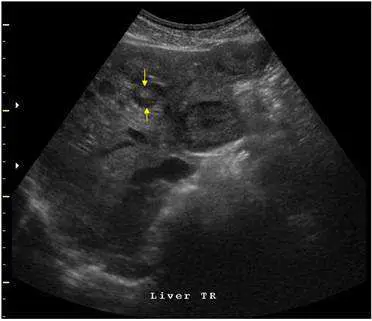

大腸癌之病人接受腹部超音波掃描如下圖,箭號所指最可能位於那個位置?

本圖標注為「Liver TR」(肝臟橫切面),為標準腹部超音波橫切掃描。圖中可見:

- 整體結構:在橫切面上可辨識肝臟左葉(left lobe)區域,肝實質回音均勻。

- 箭號指示:兩枚黃色箭頭指向肝臟左葉內側(medial)區域的一個稍高回音(hyperechoic)病灶,病灶邊緣輪廓相對清晰,大小約 1–2 cm,周邊可見略微低回音暈(hypoechoic halo),符合大腸癌肝轉移的典型超音波表現。

- 解剖定位:在橫切面上,左葉內側段(medial segment of left lobe)即 Segment 4,其解剖邊界為:

- 左側:鐮狀韌帶(falciform ligament)

- 右側:肝中靜脈(middle hepatic vein)

- 後方:門靜脈左支(left portal vein) 箭頭指示病灶位